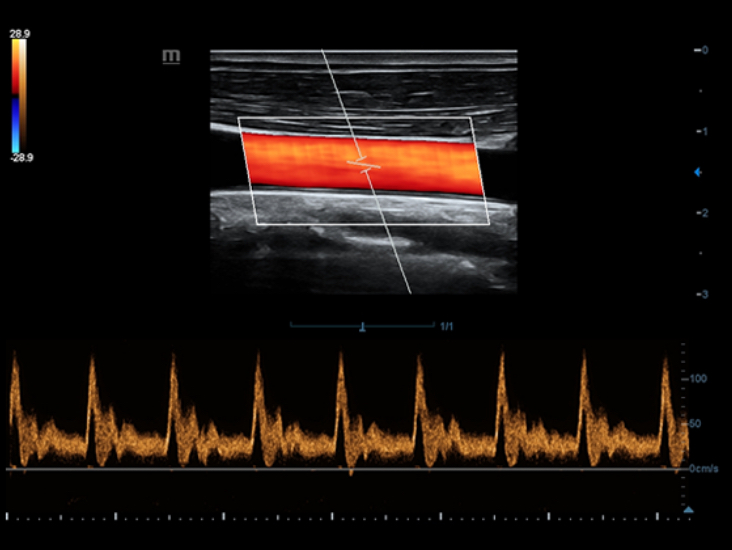

Klinische Bilder